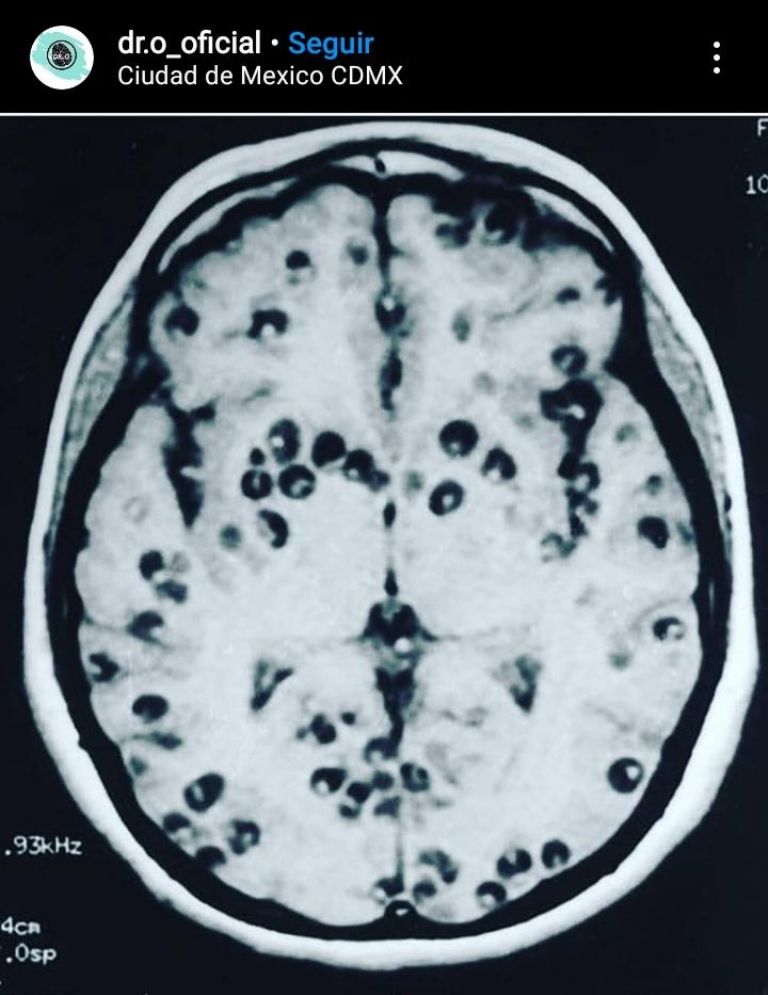

¿Comiste carnitas? Revisa los daños que puede provocar la cisticercosis

La cisticercosis es una enfermedad que se puede encontrar en la carne de puerco; conoce qué es y cómo prevenirlaCiudad de México.- La cisticercosis es una infección provocada por un parásito que se encuentra en alimentos contaminados o bien en heces fecales con la presencia de los huevos y el parásito taenia solium, a continuación sabrás un poco más sobre los métodos de contagio y cómo puedes prevenirlo.

Primero que nada es necesario repasar que la cisticercosis puede provocar convulsiones o síntomas muy parecidos a los de un tumor cerebral, disminución considerable en la vista o ceguera, y en ocasiones un ritmo cardíaco irregular o insuficiencia cardíaca.